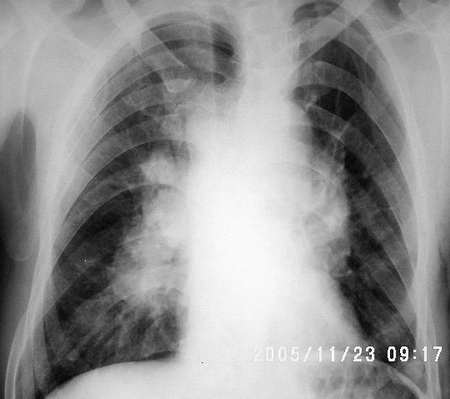

男 40 胸闷 咳嗽半年 物理检查无阳性发现

临床资料:男,40岁,胸闷,咳嗽半年,余无异常

影像表现:双侧肺门对称性增大,双肺野内纹理增强

诊断:结节病

鉴别诊断:1)淋巴瘤:以纵隔淋巴肿大较为突出

2)淋巴结结核:通常以侵犯一侧为主

3)肺部淋巴性转移:肺门淋巴结肿大多显影不清楚,且有它处转移

病史:男 40 胸闷 咳嗽半年

征象:右肺门明显肿大,右上纵膈增宽并见软组织影,左肺门增大不明显或略大。

考虑:结节病,中青年多见,常侵犯肺、双侧肺门淋巴结,纤维支气管镜检查活检。此外,血清免疫球蛋白增高、高血钙症、高尿钙症、碱性磷酸酶增高等对诊断有一定的意义。

结果 结节病 病人提供外院ct片经激素治疗好转